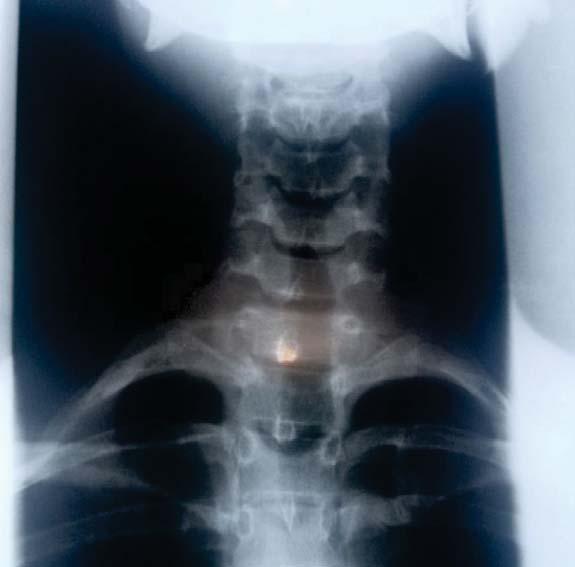

n día al despertar, percibí que tenía llagas en la boca, esto comencé a sentir picazón en el cuerpo, pensé que era alguna reacción alérgica a algo que comí. Fui al médico y me aplicaron unas inyecciones, luego me mandaron a la casa. Después de 6 horas comencé a hincharme, me aparecieron manchas rojas en el cuerpo, me empezó a faltar el oxígeno y me llevaron de nuevo al hospital; quedé algunos días en observación.

Me dijeron que consultara a un reumatólogo, me realizaron todos los exámenes inmunológicos y me diagnosticaron Lupus positivo, artritis reumatoide y síndrome antifosfolipídico.

Luego de eso mi estado de salud empeoró, no conseguía levantarme de la cama y aun acostada sentía muchos

dolores.

Un día casi muero en los brazos de mi esposo, tuvieron que llamar a una ambulancia porque me faltaba el oxígeno.

Yo estaba sorprendida con todo lo que me estaba pasando, pues tenía conocimiento que esa enfermedad no tenía cura, pero como ya asistía a la Iglesia, sabía que la última palabra la tenía Dios. Como cualquier ser

humano lloré por esta situación.

Luego fui a la Iglesia y hablé con Dios, le entregué mi vida y le dije que sólo Él podía ayudarme. Decidí usar mi fe, entregué mi certeza de que estaba curada. Poco tiempo después me volví a realizar exámenes y el

resultado salió negativo, el médico dijo que podía seguir mi vida con normalidad, estaba asombrado porque el diagnóstico anterior que había salido positivo.

Hoy estoy completamente curada, feliz junto a mi familia y haciendo lo que más me gusta, servir a Dios y ayudar a quien necesita de Él.

¡Dios nunca desampara a Sus hijos!

9 «antes «después